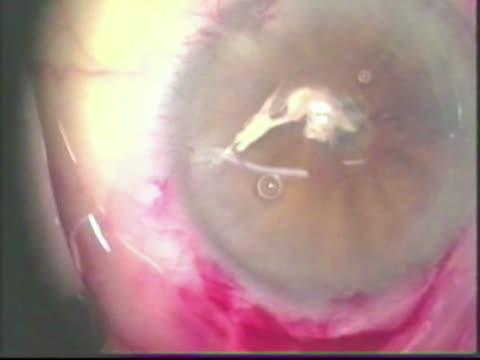

Glued IOL

Lisa Arbisser, MD